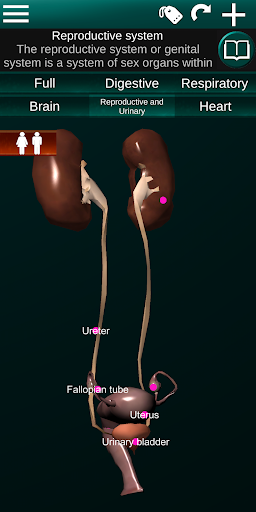

Shows a 3D anatomical model of the main organs of the human body and a description of each one.

* Reproductive system, which includes the male and female reproductive organs.

* Compare male and female organs.